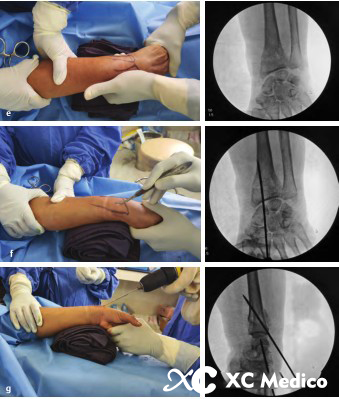

Первый K-провод вводится в бугорку Листера, наклонен при 45 ° и направлена на пальмовую кору проксимального фрагмента кости на длинной оси радиуса. Если точка вставки находится на локтевой стороне бугорки Листера, сухожилие Extensor Ollicis может быть повреждено.

Вторая K-провода вставлена 0,5 см дистальна к радиальному стилоидному процессу, K-провода находится под углом 60 ° к радиальной оси и проникает в локтевую кору, проксимальную к перелому.

Третий K-провода фиксируется к фрагменту Lunate Fossa Bone 0,5 см дистально до линии сустава запястья, расположенной между четвертым и пятым компартментами разгибателей. K-провода прикреплена к ладонильной стороне радиуса под углом 45 °, как показано на рисунках A и B ниже.

Классическая чрескожная фиксация проволоки Киршнера расстановки дистального радиуса показана на рисунках AE ниже.